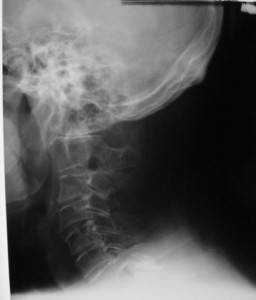

- When to know if there may be no atlas at all?! (see x ray below)